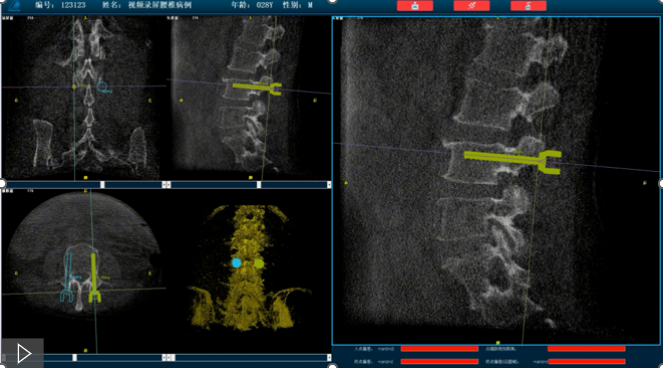

首先,需要明確的是機器人手術,機器人在術中還是做輔助性操作,術前基于三維C形臂等影像掃描得到骨骼結構的三維數據,機器人系統利用手術規劃軟件,引導醫生進行可視化預手術規劃(釘道規劃、入釘角度),選擇合適的螺釘規格、尺寸,輔助評估和及時調整手術路徑規劃設計,整臺手術都是在主刀醫生的把控下進行操作的。機器人系統不僅靠譜,而且還提升了手術的安全性、機械臂的精準以及力傳感識別、實時動態追蹤等保護技術,增加了手術的準確性和安全性。

就以普愛醫療骨科機器人PL300B為例,骨科機器人可以保證亞毫米級精準度,例如在脊柱上植入椎弓根螺釘,傳統手術需要暴露骨組織解剖結構,往往會有10-20cm的開口,而使用了手術機器人可以將開口轉變為數個1-2cm的開口,出血量降低至95%以上,大大降低并發癥的發生率,同時有益于病患的更快的術后恢復。